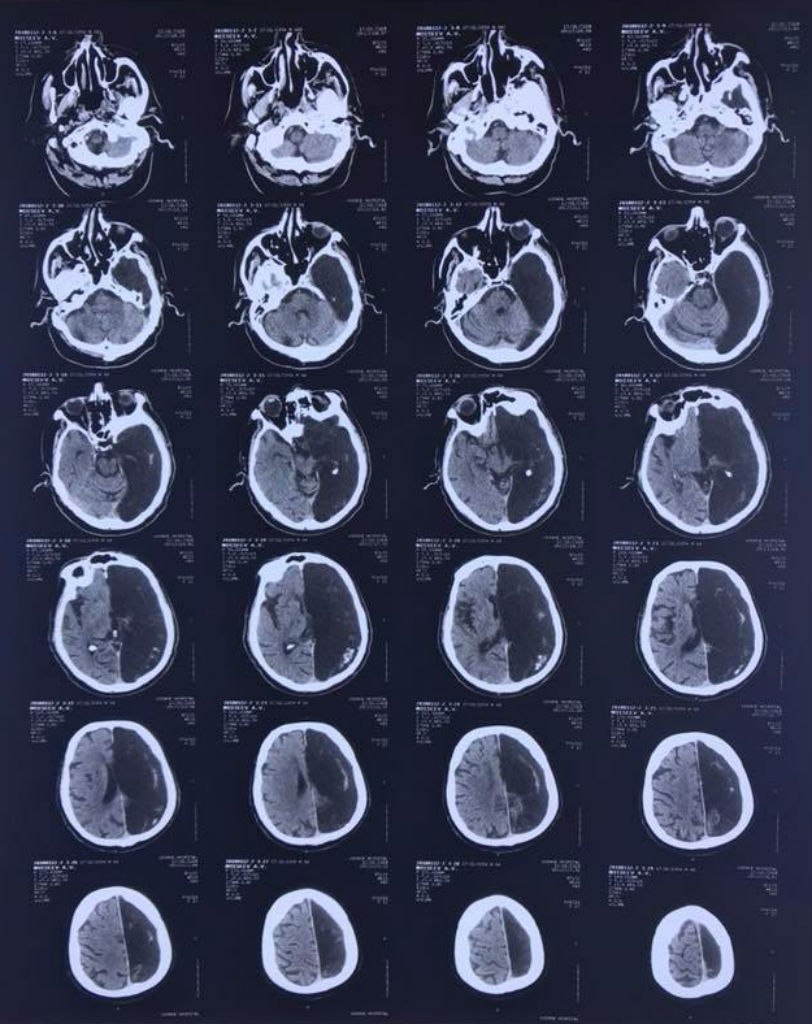

В подмосковную больницу попал пациент с нарушением кровообращения мозга. Когда врачи провели компьютерную томографию, то увидели, что у пациента нет одного полушария. О необычном клиническом случае сообщает «Московский комсомолец» со ссылкой на невролога Федерального центра экстрапирамидных заболеваний и психического здоровья ФМБЦ им. А.И.Бурназяна Марину Аникину.

Когда радиологи сделали ему КТ, то некоторое время пребывали в недоумении — у пенсионера отсутствовала та часть мозга, где произошла та самая ишемическая атака.

Вместо левого полушария на снимке зияла черная «дыра». Неврологи сделали вывод, что функции всего мозга у этого человека всю жизнь выполняло только оставшееся правое полушарие».